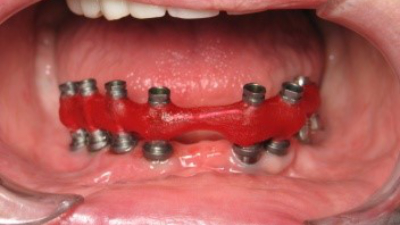

Decontamination (with a dental laser) and graft case of moderate peri-implantitis

In this video, Dr. Scott Froum treats a case of moderate peri-implantitis using a 9.3-micron CO2 laser along with hard-tissue grafting and bio-PRF growth factors.

Oct. 11, 2023